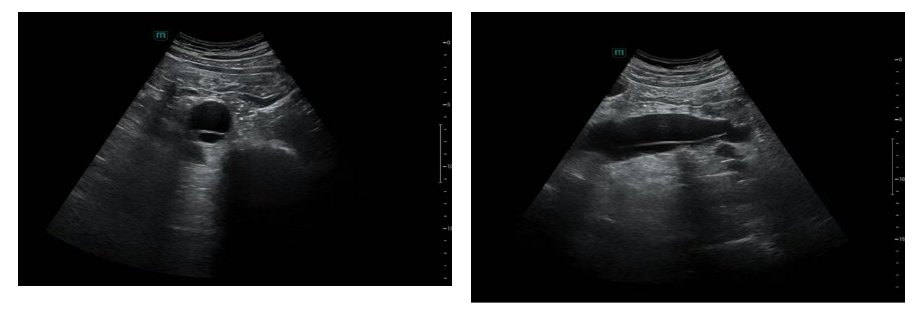

近日,一位青年男性患者因肝硬化来到北京地坛医院徐州医院(徐州七院)超声医学科进行常规超声复查。科室主任潘国栋有一个小习惯,在对检查部位进行扫查评估的同时,也会对毗邻脏器和大血管状态进行查看。当探头扫过上腹部椎体前方区域时,潘国栋敏锐地捕捉到腹主动脉的影像存在异常:管腔内可见一条高回声飘带影,将血管腔分隔开来,这高度提示着一种极其凶险的疾病:主动脉夹层!

超声危急值!意识到病情的极端危重性(主动脉夹层破裂死亡率极高,每小时增加约1%),潘国栋迅速与科内王慧医生会诊、复核图像,确认从腹腔干分叉水平到髂血管分叉水平均可看到异常的内膜回声后,立即按照医院危急值报告制度启动应急流程,第一时间通过危急值上报系统,将“疑似主动脉夹层”的危急值结果报告给患者的主治医生,并致电临床医生描述超声所见,强调病情的紧迫性和危险性,建议立即行进一步确诊检查。在确保安全的前提下,简明告知患者发现严重问题需紧急处理,稳定其情绪,避免剧烈活动。